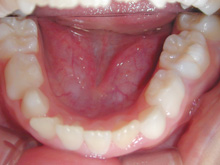

ストリッピングを行うことなく上下顎の前歯の叢生は改善されました。

上顎両側側切歯の歯肉の腫れは消退し、下顎前歯の叢生の改善により歯肉の腫れは消退傾向がみられます。

今後は上顎中切歯の歯間乳頭の腫れを軽減するためブラッシング指導と保定治療時のPMTCを継続する予定です。

矯正歯科治療で歯列が改善されたことで歯口清掃が容易になり、常用薬剤の副作用である歯肉腫脹は軽減されています。

治療費用:50万円

動的治療期間:1年6か月